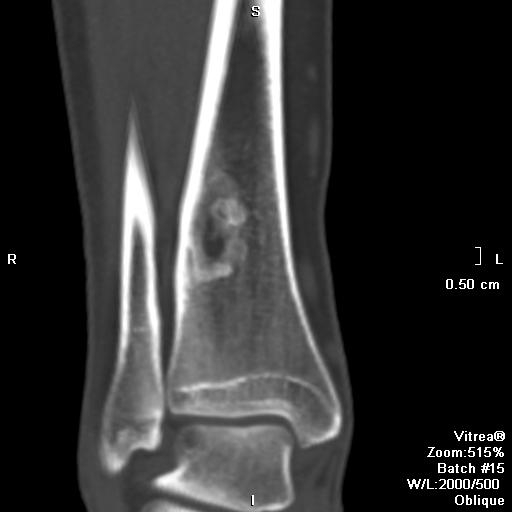

- Компьютерная томография (КТ). КТ может быть назначена для точной оценки костных структур, например, для измерения торсии (скручивания) бедренной и большеберцовой костей или для точного расчета расстояния между бугристостью большеберцовой кости и центром межмыщелковой борозды (индекс TT-TG).